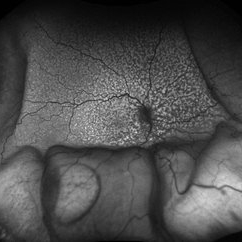

Idiopathic Uveal Effusion Syndrome

61 year old male with Idiopathic Uveal Effusion Syndrome with starry night appearance on fluorescein. 3 weeks s/p single external drainage retinotomy and 9 weeks of oral pred with recurrent choroidal effusions. Has since returned to surgery for secondary drainage retinotomy; subretinal fluid remain persistent.

Photographer: Jordyn Beckman

Imaging device: Optos California

Condition/keywords: chorioretinitis, Choroidal, exudative detachment, window defect